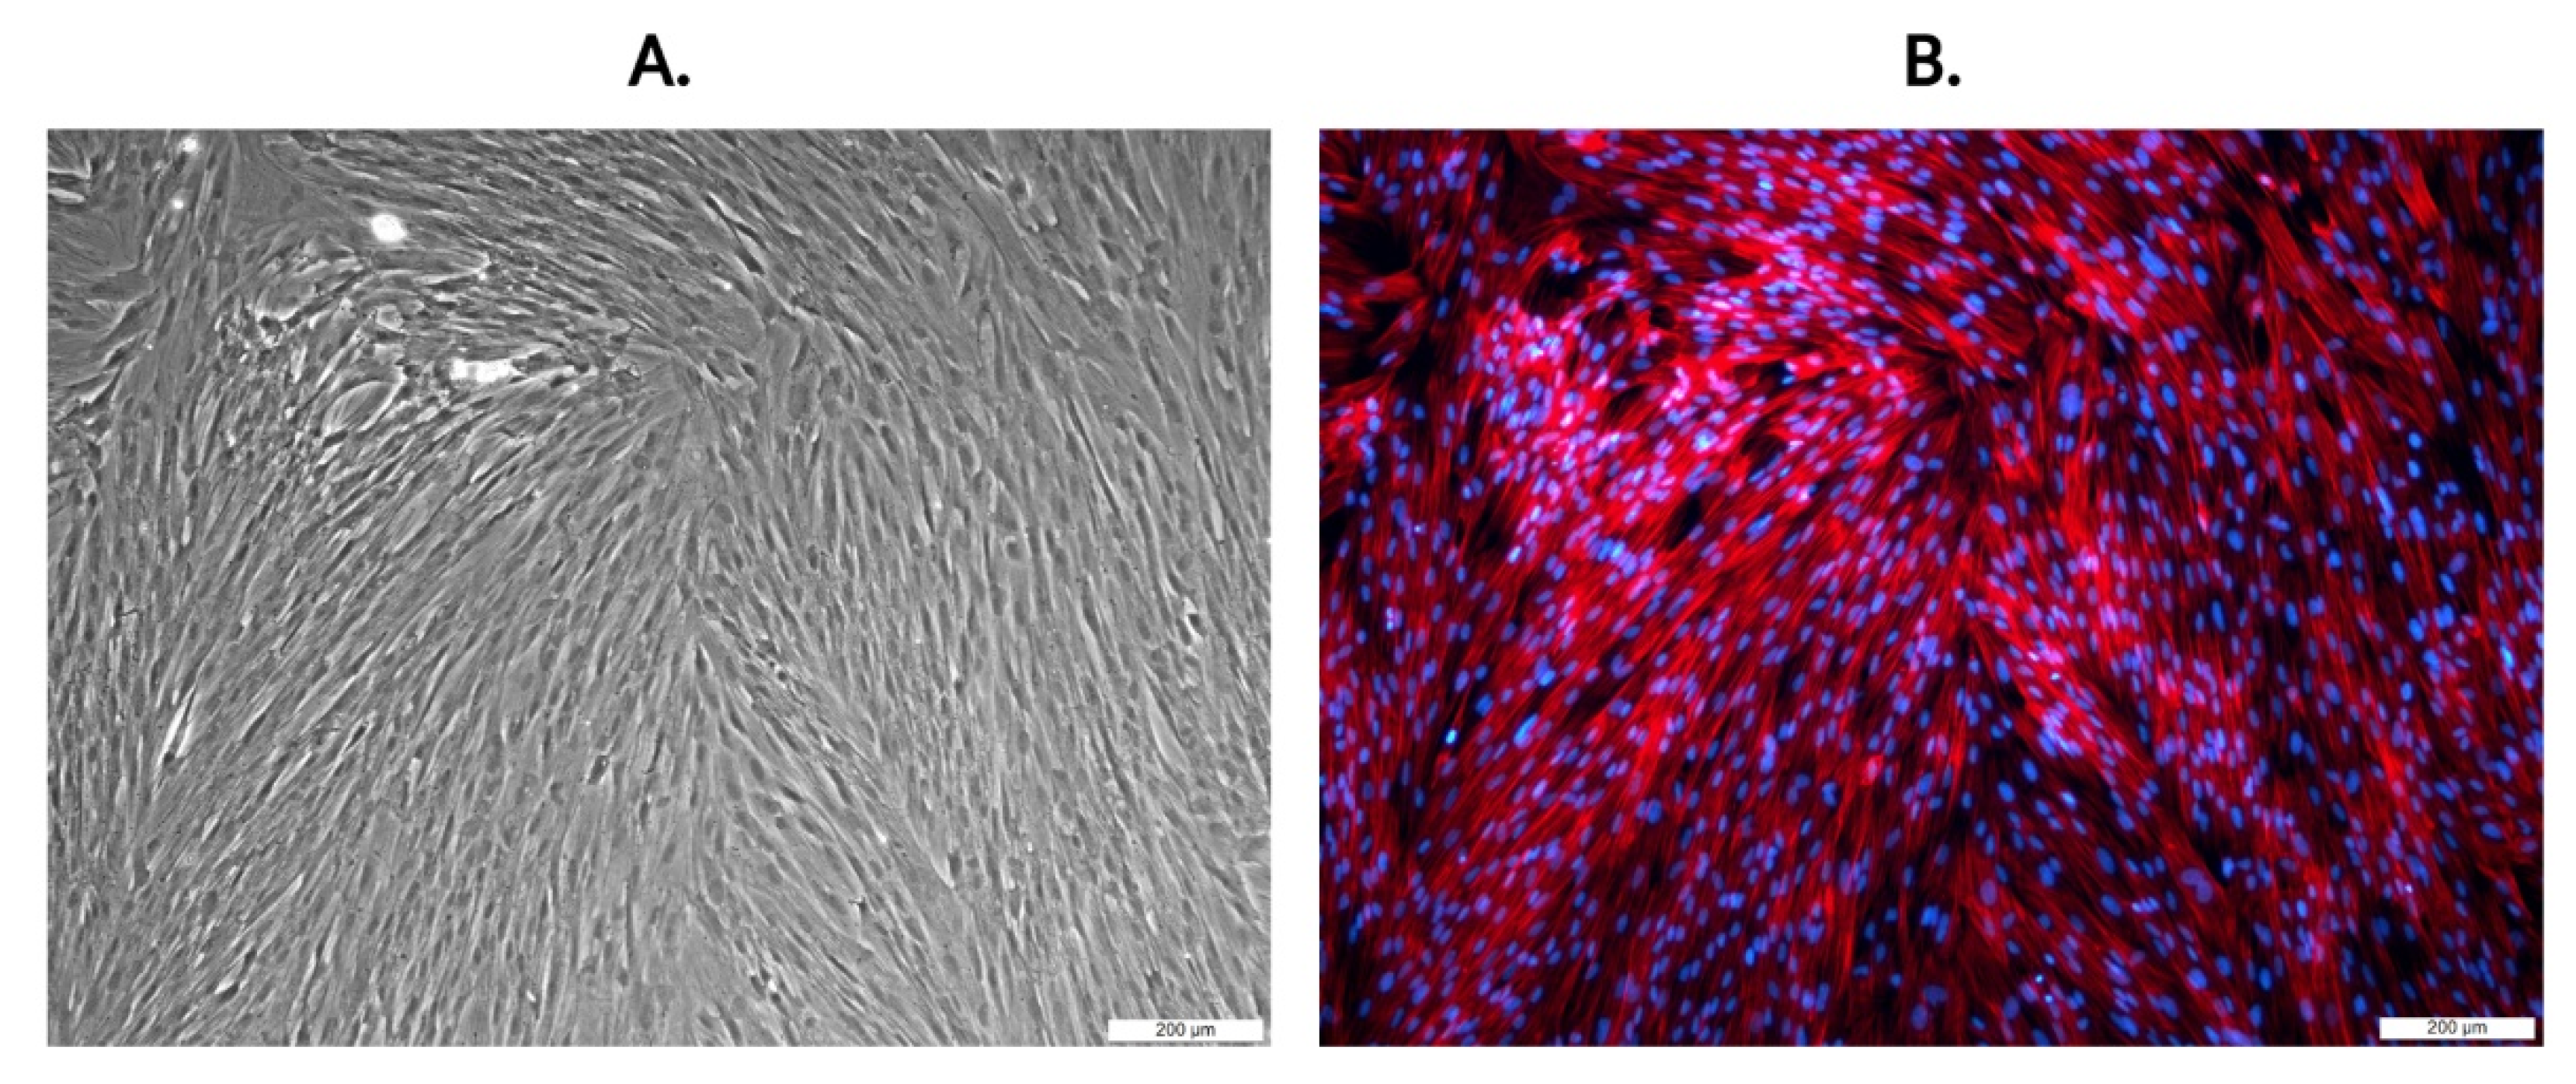

2.1. The Identification of Human Chorionic-Derived MSCs